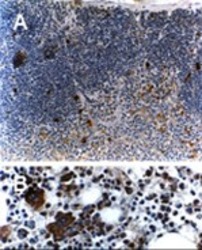

Immunohistochemistry

AP22310SU-S IHC